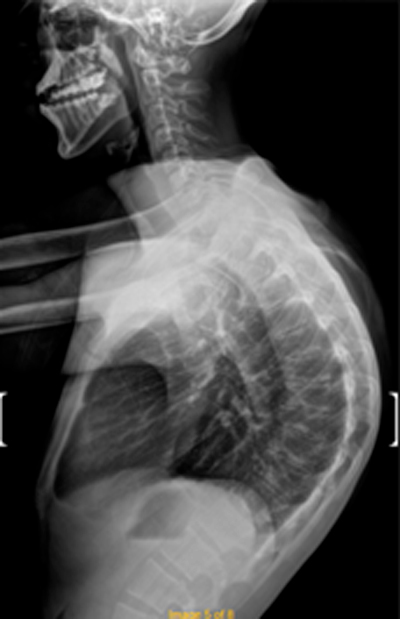

DIAGNOSI:

IPERCIFOSI DORSALE GRAVE

Radiografia dorsale pre operatoria

Intervento chirurgico eseguito:

STABILIZZAZIONE DORSO – LOMBARE CON OSTEOTOMIE CORRETTIVE

Radiografia dorsale post-operatoria